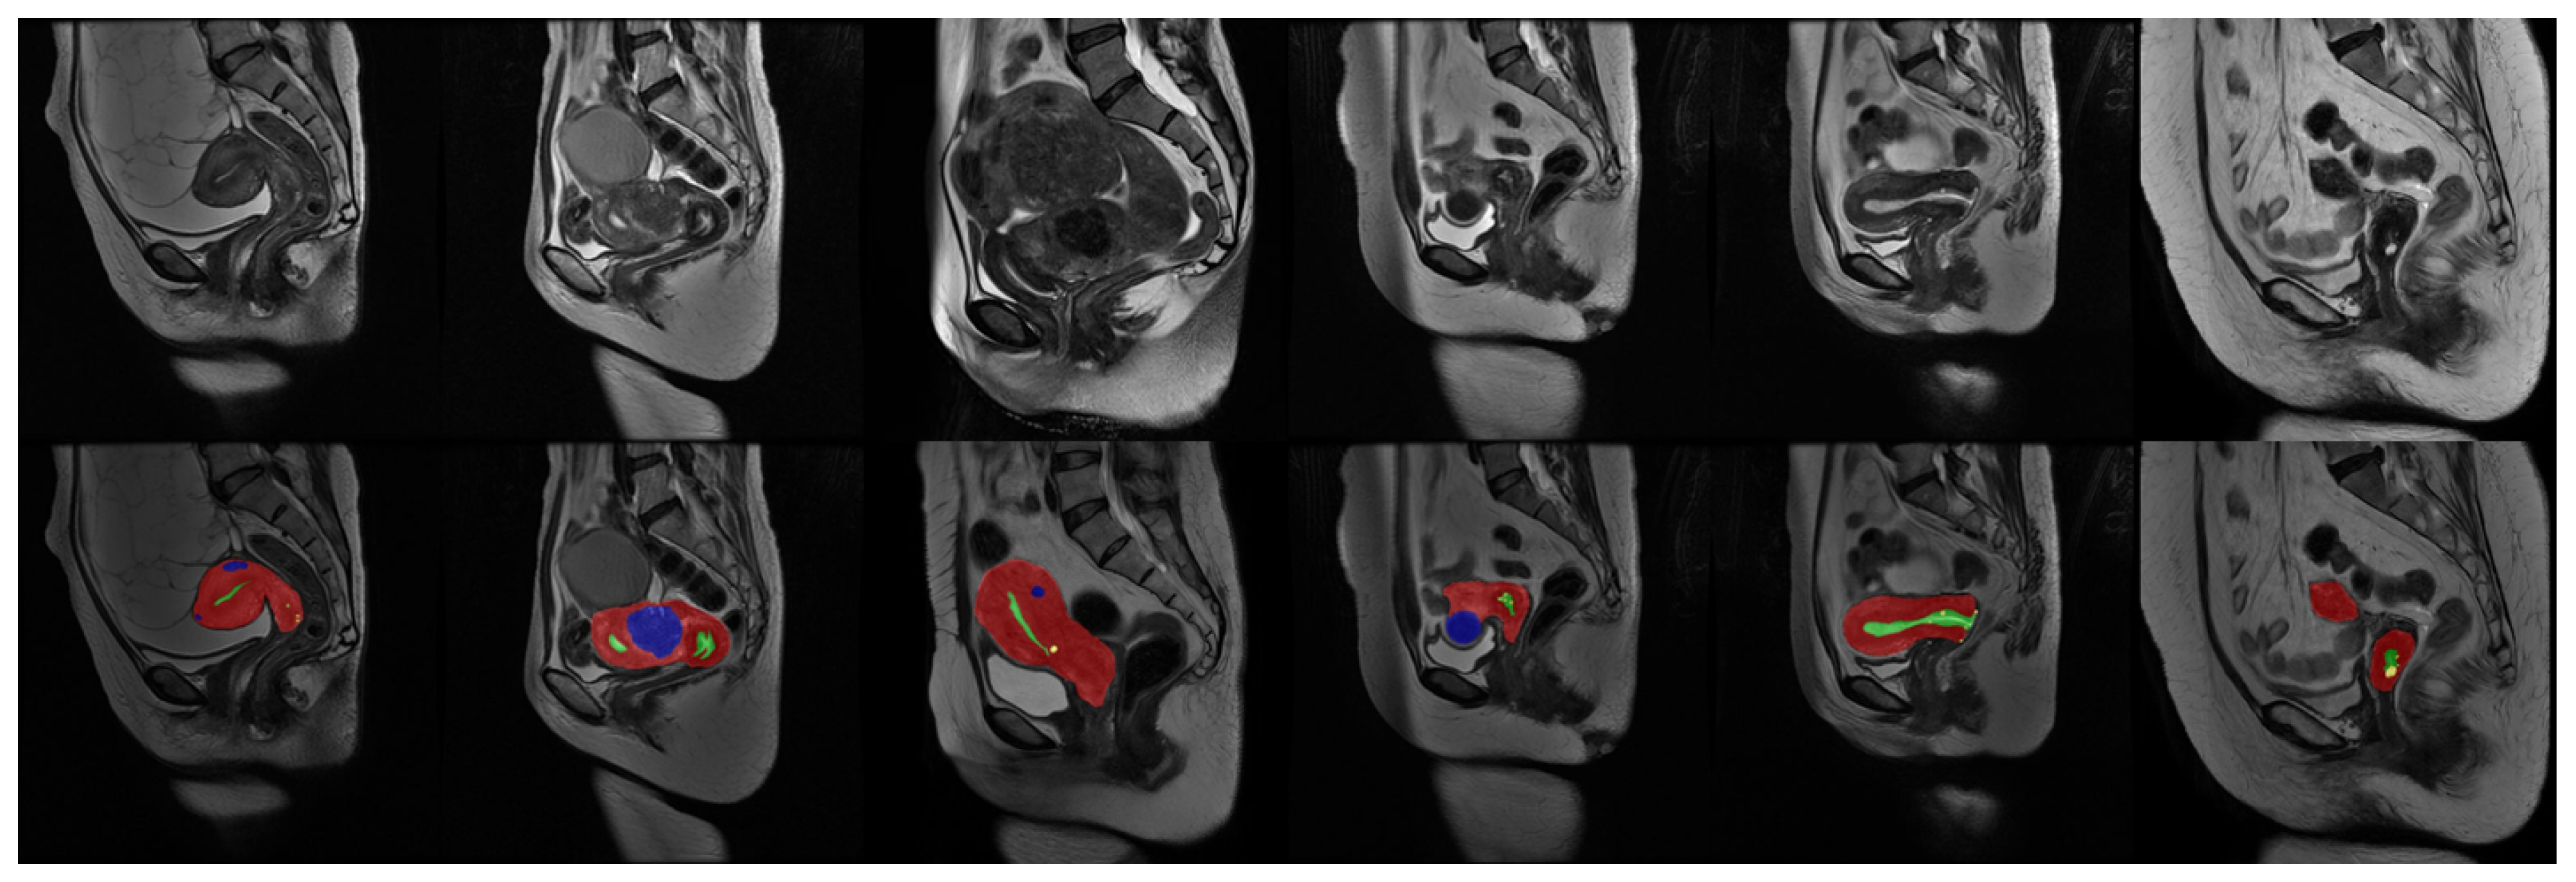

Our uterine MRI dataset comprised a total of 3206 original grayscale MRI images, each accompanied by its corresponding annotated counterpart. The dataset encompassed four distinct classes, namely the uterine wall, uterine cavity, myomas of the uterus, and nabothian cysts. Each class was assigned a specific pixel value (1, 2, 3, 4) within the real-valued images. To establish a clear division, the dataset was partitioned into a training set and a validation set, with a ratio of approximately 6:1. The training set consisted of 2738 images, while the validation set comprised 468 images. It is important to note that certain images solely depicted the background and were, thus, removed prior to training. Consequently, the effective training set encompassed 1036 images. Figure 6 provides a partial sample showcasing some images from the dataset.

Figure 6. Data sample: The first line is the original image, and the second line is the real value image after visualization. During visualization, the uterine wall was covered in red, the uterine cavity was covered in green, myomas of the uterus were covered in blue, and nabothian cysts were covered in yellow.